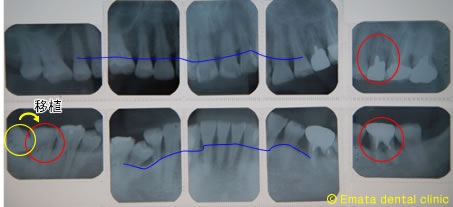

患者様は赤色が重度の歯周病、青色が初期から中等度の歯周病で来院されました。残念ですが赤色は抜歯の適応です。患者さんは健全な歯をけずりたくない、歯周病の歯にブリッジや義歯をいれ負担がかかりまた歯の喪失はいやなので、歯牙移植、インプラントを希望されました。

治療前のレントゲン(10枚法)

歯周病の進んだ部位へのインプラント治療は、骨の喪失が大きく、骨を造る治療(GBR 、ソケットリフト、サナスリフト、骨移植など)が必須になります。